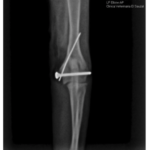

Fractura de cóndilo humeral y epicóndilo medial en un perro miniatura, tratada con una tornillo y una aguja de kirshner